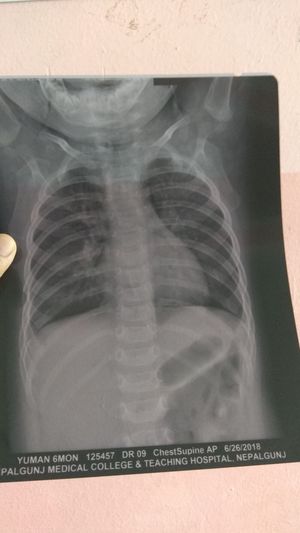

What do yuh guys find here??

2nd post in 1 day with patient's information all over(a minor nevertheless 😩), how did you not simply think to crop that lower part out ?? Dont you know the importance of protecting patients privacy ??